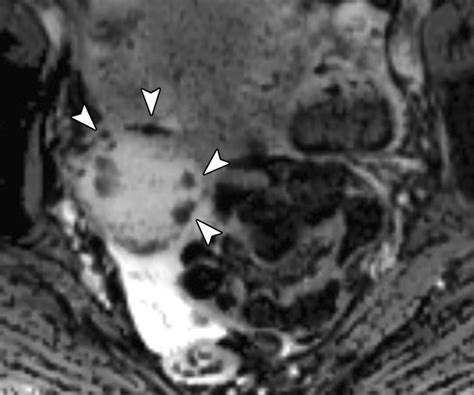

• Neurodegenerative Disorders: By quantifying iron deposition in the basal ganglia, clinicians can monitor conditions such as Alzheimer’s, Parkinson’s, and Multiple Sclerosis.

• Brain Tumors: SWI helps differentiate between tumor types by assessing the degree of intratumoral hemorrhage and the organization of the microvasculature.

Radiologists look for "blooming effects" on the images, where small, dark spots represent paramagnetic substances like blood products. Because the signal decay is accelerated in regions with high iron or deoxyhemoglobin content, these areas appear as dark, high-contrast signals. Interpreting these images requires an understanding of how to differentiate between normal venous blood and pathological hemorrhages. For instance, the presence of blood in deep brain nuclei versus the cortex can indicate vastly different underlying etiologies, such as hypertensive vasculopathy or cerebral amyloid angiopathy.